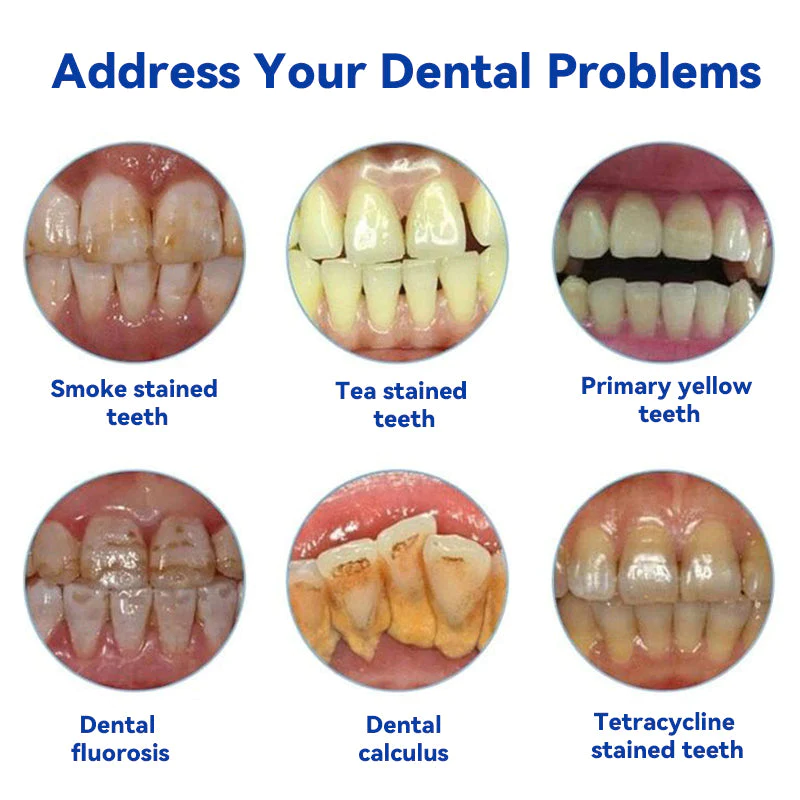

What Makes Oraliz Toothpaste the Top Choice?

Oraliz anti-cavity toothpaste with mint scent utilizes a combination of bioactive silica, oral probiotics adp-1, and zinc citrate to protect against cavities, promote gum health, and freshen breath. Bioactive silica helps to strengthen tooth enamel, while oral probiotics adp-1 support a healthy oral microbiome. Zinc citrate helps to reduce plaque and neutralize bad breath. Regular use of this toothpaste can lead to improved overall oral health.